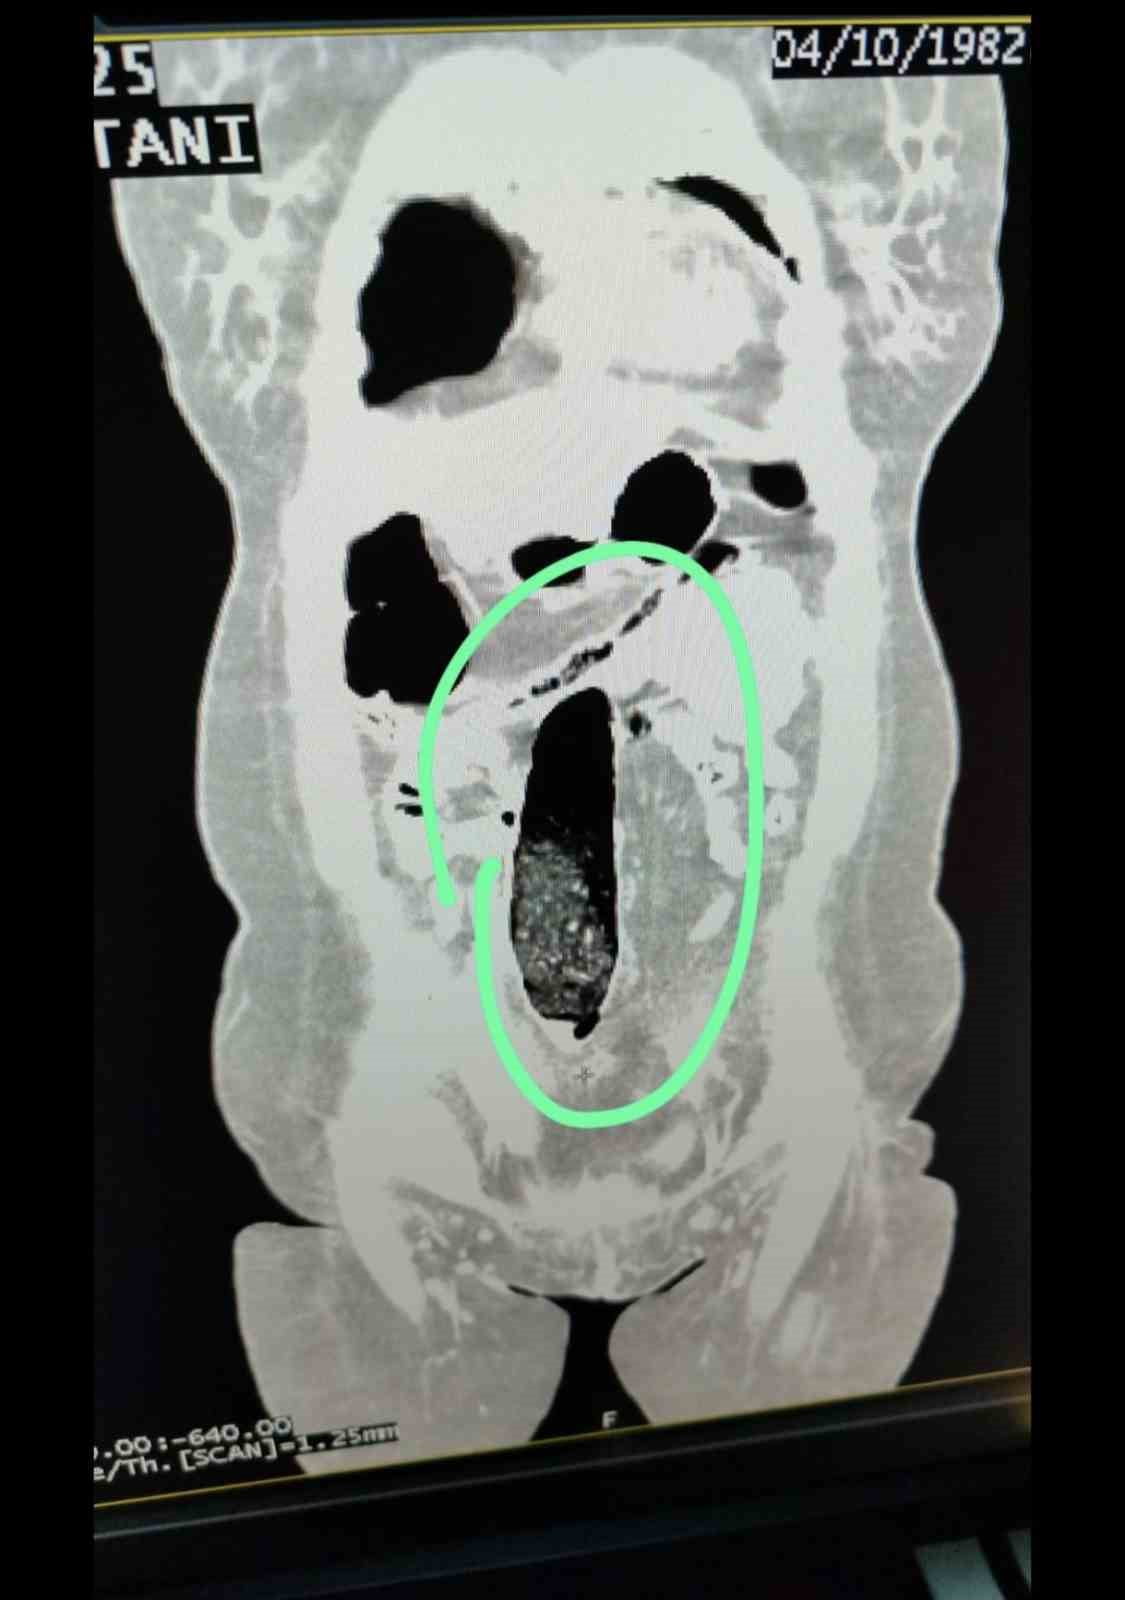

Otobüste bulunan 2 İran uyruklu şahıs üzerinde yapılan kontrollerde şüpheli durum tespit edildi. Gerçekleştirilen iç beden muayeneleri sonucunda şahısların vücutlarının doğal boşluklarında ve bağırsaklarında uyuşturucu madde bulunduğu belirlendi.

Tıbbi müdahale ile yapılan aramalarda; F.V. isimli kadın şahıstan 3 parça halinde toplam 397,78 gram metamfetamin, S.İ. isimli erkek şahıstan ise 24 adet sentetik hap ile 3 parça halinde toplam 167,68 gram metamfetamin ele geçirildi.